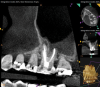

Periapical and CBCT imaging confirmed the presence of apical pathology, as well as a dramatic sinus communication with MSEO (Figure 1 and Figure 2). The diagnosis for tooth No. 13 was pulpal necrosis with asymptomatic apical periodontitis. NSRCT was completed (Figure 3). At the patient's 1-year follow-up appointment, tooth No. 13 remained asymptomatic, her sinusitis was resolved, and complete radiographic healing of both periapical pathology and the MSEO was noted (Figure 4).

Fig 2. Preoperative CBCT. Note periapical pathology associated with tooth No. 13 communicating with the adjacent maxillary sinus along with associated mucositis.

Figure 2